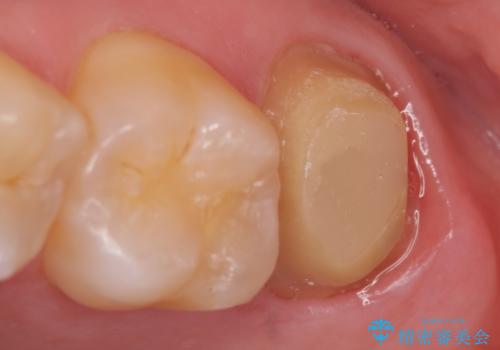

- 左上の奥歯が腫れぼったく、ものを咬むと痛むので診て欲しいといらっしゃった方の症例です。

診査の結果左上7は神経が死んでいたため、根管治療を行いました。

症状の緩解を確認後、オールセラミッククラウンによる補綴を行いました。